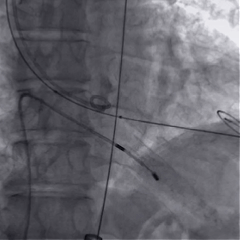

术中影像

瓣膜稳定释放

瓣膜展开后造影

再次造影,确认瓣膜位置